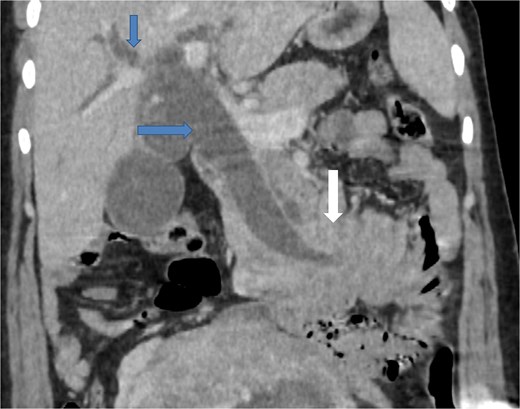

Due to the acute presentation and unavailability of emergency magnetic resonance imaging (MRI), a contrast-enhanced computed tomography (CT) scan of the abdomen was performed with strict fetal protection measures (lead apron, low-dose protocol). The pancreas appeared normal with no signs of inflammation, necrosis, or peripancreatic fluid. Unexpectedly, the scan revealed a duodenojejunal intussusception, likely originating from the fourth portion of the duodenum (D4), involving invagination of a proximal jejunal loop (Fig. 1). A typical pseudokidney sign was observed on sagittal reconstructions (Fig. 2). There was no identifiable lead point such as a mass or polyp. The intussusception was seen tractioning the distal common bile duct, leading to marked extra- and intrahepatic bile duct dilatation (Fig. 3).

Axial contrast-enhanced CT image showing a duodenojejunal intussusception (arrow), originating from the fourth portion of the duodenum and involving invagination of a proximal jejunal loop.